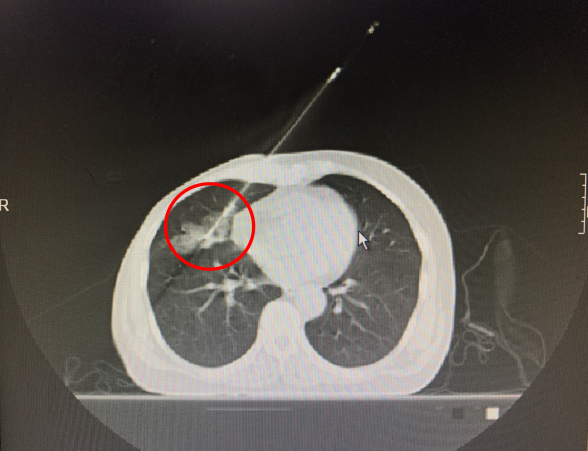

穿刺针紧贴心脏,一击中靶!

病理结果回报:肺浸润性腺癌。

经过小组讨论和推演,最终决定不走寻常路,在确保安全可行的条件下,从体表胸骨心脏旁路进针,循序渐进调整进针深度和角度,反复指导病人配合呼吸运动,不断调试穿刺针角度和深度。终于在紧张有序中成功穿刺,发现肺内有少量出血。为了确保穿刺组织可靠性,继续挑战完成第二针穿刺。整个过程中患者未发生气胸、咯血、心脏损伤等可能危及生命的严重并发症。

最终穿刺病理显示:浸润性腺癌,考虑原发性支气管肺腺癌。李阿婆明确为第二肿瘤,全身评估后确诊为早期肺癌。随后李阿婆转入胸外科行肺叶切除术,得到了最合理和有效的治疗。